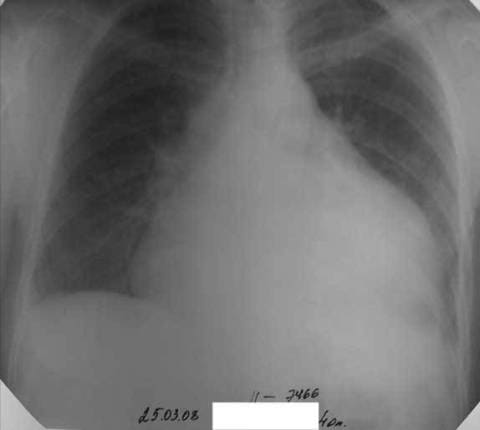

При рентгенографии органов грудной клетки определяется увеличенное в размерах сердце в остром периоде, при экссудативном перикардите за счет скопления жидкости.

Рентгенография органов грудной клетки при экссудативном перикардите

При уплотнении перикарда сердце уменьшается в размерах, возможно появление очагов обезыствления. Эхокардиография является золотым стандартом для определения перикардиального выпота и, в последующем, оценки динамики заболевания при лечении. В трудных случаях рекомендована компьютерная томография и магниторезонансная томография сердца.